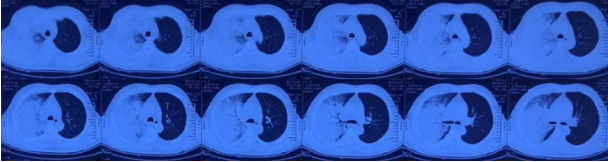

尿军团菌抗原(+)。入院第2天:无创机械通气通气,FiO2 100%;第3天气管插管,有创机械通气,FiO2 100%,PEEP 13 cmH2O。第4天,FiO2 45%,PEEP 8 cmH2O。逐渐降低支持力度,插管第7天撤机,拔管。拔管5天转入普通病房。整个病程中患者发热症状持续14天。患者入院前后胸部影像学变化如图2所示。

图2  患者胸部CT变化

经过治疗,患者胸部CT仍可见双肺斑片状磨玻璃渗出影,但整体情况尚可,遂予拔管。出院前复查胸部CT可见病灶明显吸收,下肺有少许纤维条索状渗出(图3)